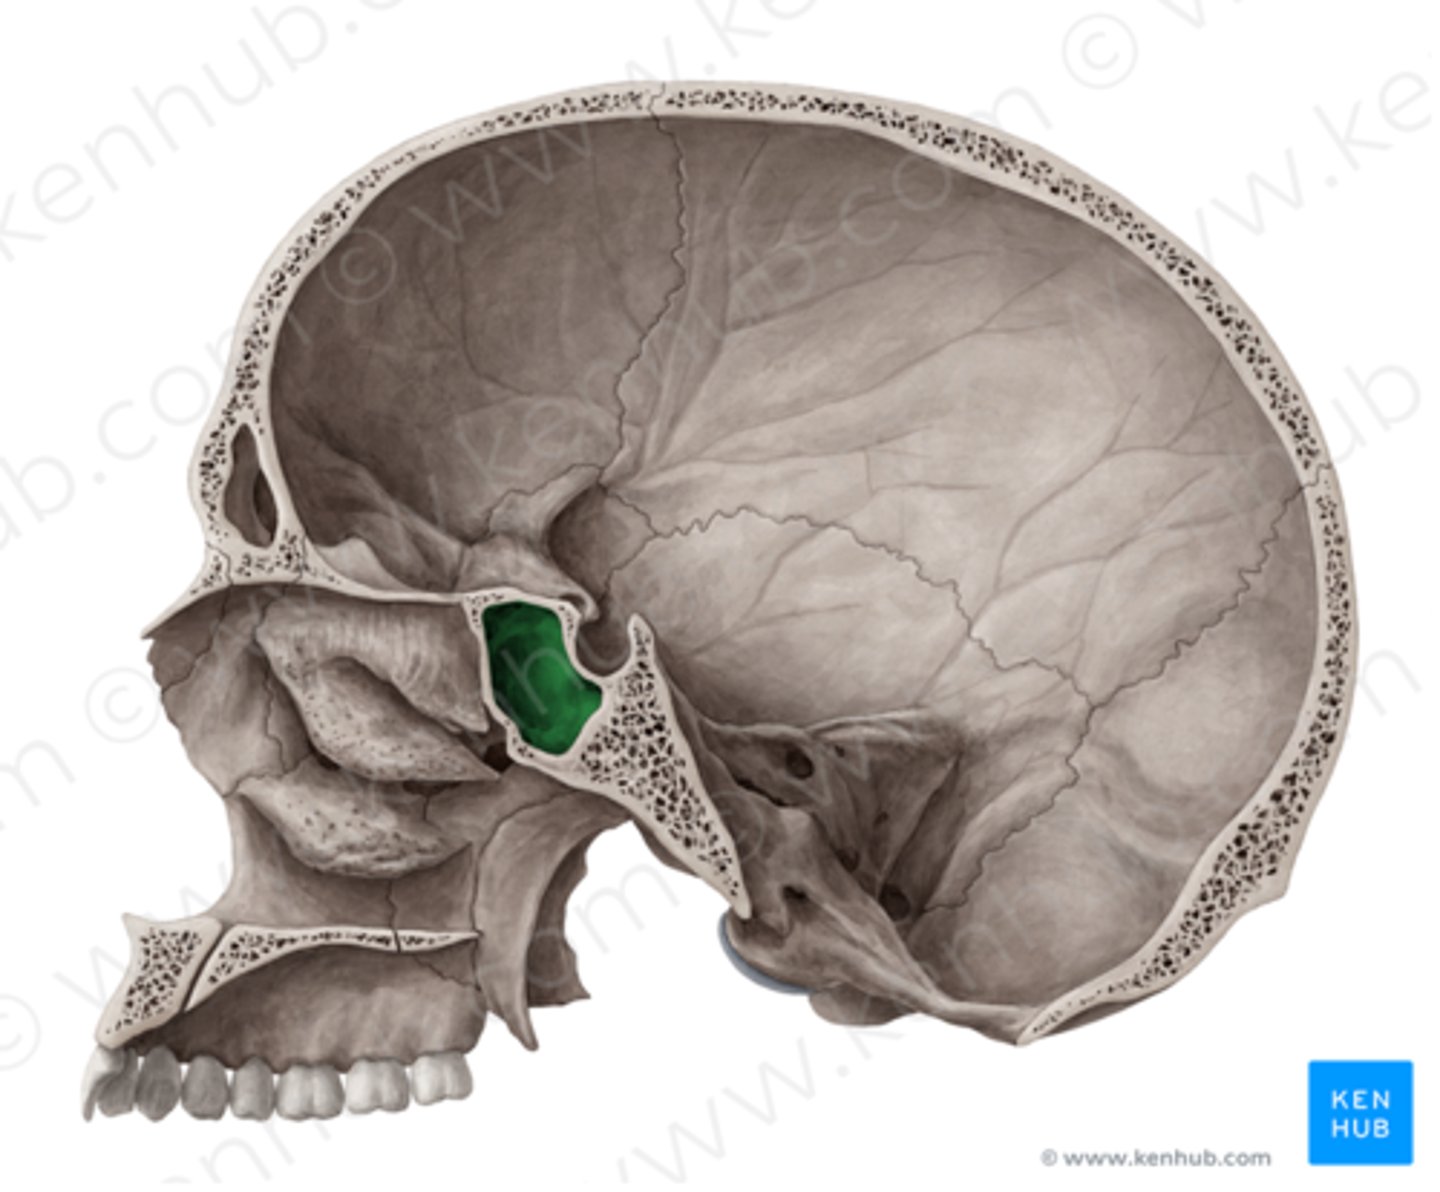

os sphenoidale

pleištakaulis

fossa hypophysialis

posmegeninės liaukos duobė

ala major

Didysis sparnas

ala minor

mažasis sparnas